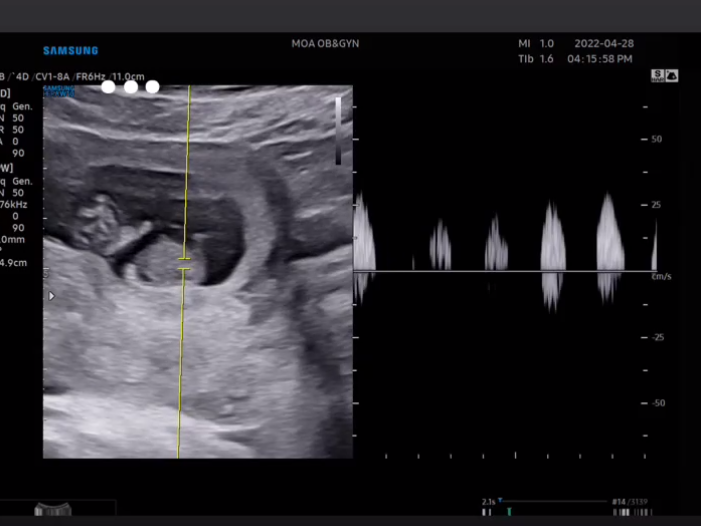

임신 9주차 초음파 사진

또 4월 28일날 촬영된 초음파 사진도 공개했습니다.

심장박동 소리 또한 인스타그램 스토리를 통해서 전했습니다.